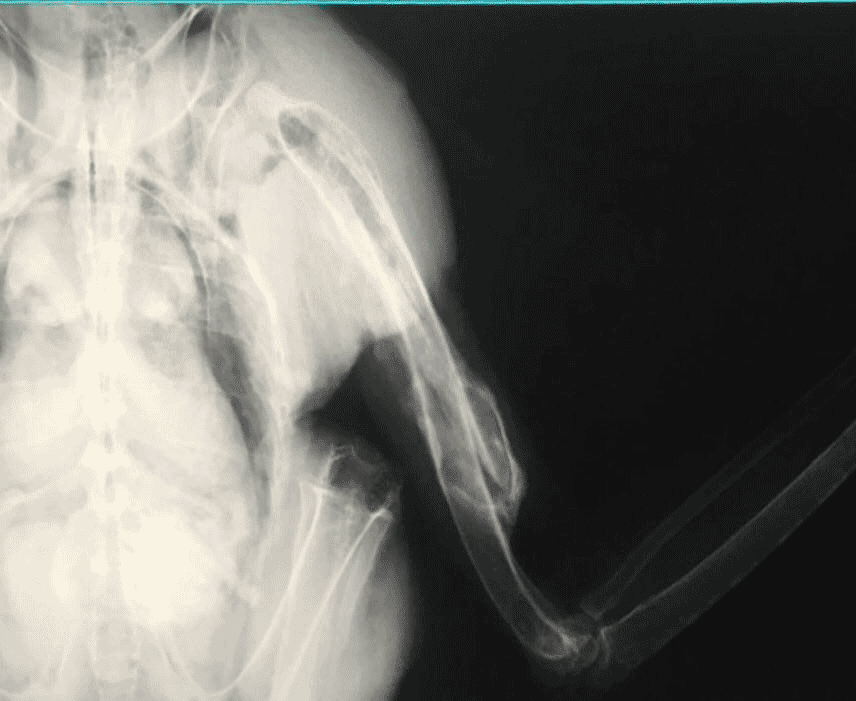

به گزارش افکارنیوز، حمیدرضا فتاحیان، متخصص جراحی دامپزشکی که عمل جراحی موفقیتآمیز ستون مهرههای پلنگ رودسر را در کارنامه دارد درباره عمل جراحی این عقاب شاهی به تسنیم میگوید: رادیوگرافی این پرنده نشان داد از شکستگی بال چپ حدود یک ماه میگذرد و استخوانها بیآنکه در امتداد یکدیگر قرار گرفته باشند جوش خوردهاند.

وی ادامه میدهد: تصاویر رادیوگراف، یک ساچمه را در گردن این پرنده شکاری ارزشمند نشان داد و یک شکستگی در استخوان پال چپ. به نظر میرسد اصابت گلوله، به سقوط این پرنده و شکستگی بال منجر شده باشد.